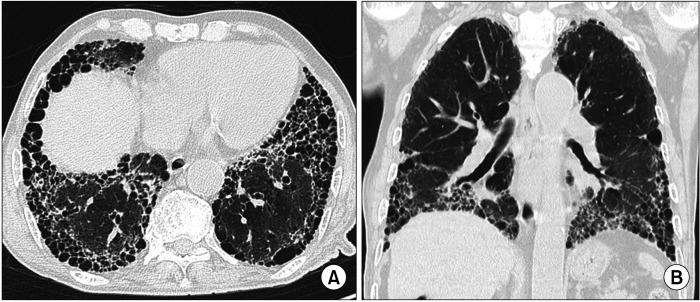

Interstitial lung disease (ILD) is often observed in connective tissue diseases (CTDs), frequently in rheumatoid arthritis, systemic sclerosis, primary Sjögren's syndrome, and inflammatory myositis. Early detection of ILDs secondary to rheumatic diseases is important as timely initiation of proper management affects the prognosis. Among many imaging modalities, high-resuloution computed tomography (HRCT) serves the gold standard for finding early lung inflammatory and fibrotic changes as well as monitoring afterwards because of its superior spatial resolution. Additionally, lung ultrasound (LUS) and magnetic resonance imaging (MRI) are the rising free-radiation imaging tools that can get images of lungs of CTD-ILD. In this review article, we present the subtypes of ILD images found in each CTD acquired by HRCT as well as some images taken by LUS and MRI with comparative HRCT scans. It is expected that this discussion would be helpful in discussing recent advances in imaging modalities for CTD-ILD and raising critical points for diagnosis and tracing of the images from the perspective of rheumatologists.

间质性肺疾病(ILD)常在结缔组织病(CTD)中出现,常见于类风湿关节炎、系统性硬化症、原发性干燥综合征和炎性肌病。早期发现风湿性疾病继发的ILD很重要,因为及时开始适当治疗会影响预后。在众多成像方式中,高分辨率计算机断层扫描(HRCT)因其卓越的空间分辨率,是发现早期肺部炎症和纤维化改变以及后续监测的金标准。此外,肺部超声(LUS)和磁共振成像(MRI)是新兴的无辐射成像工具,能够获取CTD-ILD患者肺部的图像。在这篇综述文章中,我们展示了通过HRCT在每种CTD中发现的ILD图像亚型,以及一些LUS和MRI拍摄的图像,并与HRCT扫描进行对比。期望这一讨论有助于探讨CTD-ILD成像方式的最新进展,并从风湿病学家的角度提出图像诊断和追踪的关键点。